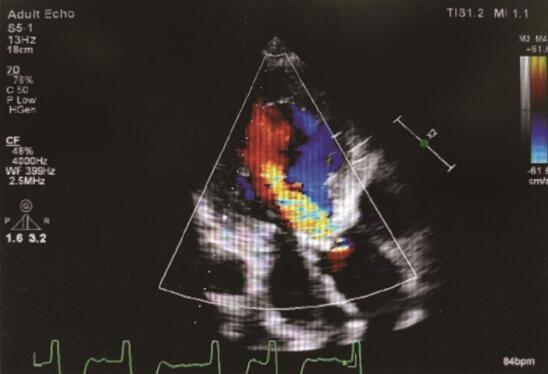

血常规:WBC 12.4×109/L,中性粒细胞百分比83.5%;尿常规、粪便常规、肝肾功能、血脂、凝血功能、C反应蛋白(CRP)、甲状腺功能均未见异常。心电图:窦性心律,心率89次/min,大致正常心电图。胸部CT示:双下肺斑片状影,感染可能性大,左肺下叶少量胸腔积液,下叶背段钙化点,局限性肺气肿。超声心动图示(图1):LV 64mm,LA 34mm,RV 19mm,RA 37mm,AO 35mm,AAO 37mm,EF 43%;主动脉瓣钙化伴中-重度反流,左心增大,主动脉增宽,二尖瓣轻-中度关闭不全。

图1 超声心动图